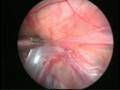

Can this operation be done laparoscopically?

Operation in hydrocele involves closing of the open passage through which the testis has come down. This can be done from outside as in open surgery or from inside by laparoscopy. With the help of laparoscopy we are able to look at the opposite side to see if the passage is open on that side as well. This can be closed at the same sitting if you wish to. Recovery from surgery, timing of surgery and discharge from hospital are the similar for open surgery and laparoscopic surgery.

However, it is important to note that an open passage does not always mean that your child will get a hydrocele or hernia on the opposite side. There is no harm in opting for a second surgery later if your child at all develops a hernia on the opposite side.